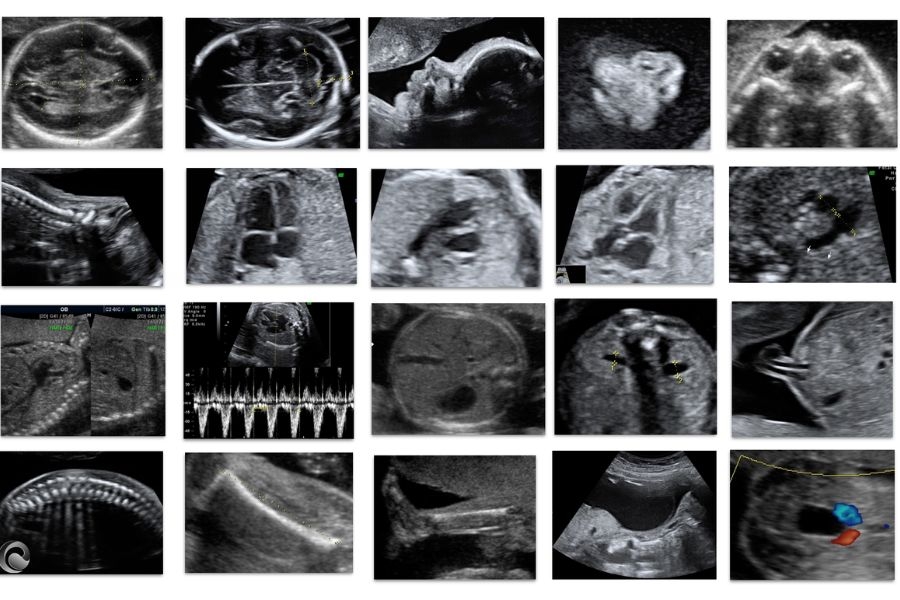

Ecografía morfológica ampliada: Desde las 12 a 41 semanas